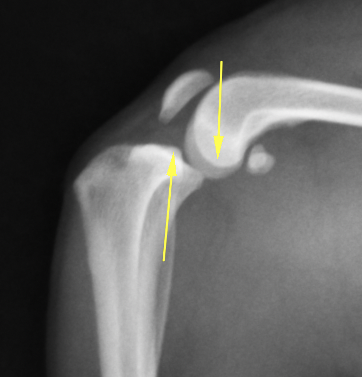

正常な膝関節のレントゲン画像です。大腿骨と脛骨のライン(矢印)がほぼ一致しているのがわかります。

前十字靭帯断裂の膝関節です。ずれているのがおわかりでしょうか?

矢印を入れたものです。正常なものと比較すると一目瞭然でずれているのがわかるかと思います。